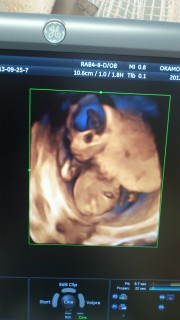

お腹がぽっこりしていてとっても可愛いです。手を耳の方に持ってきています♪